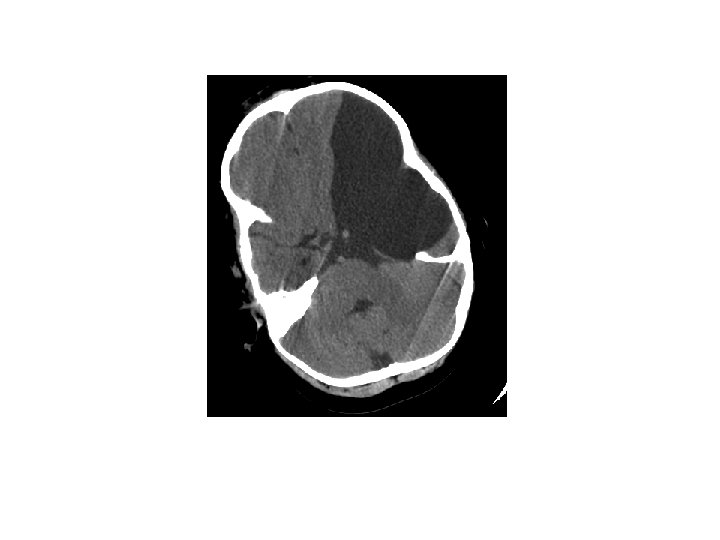

Greining • CT • MRI • Ísótóparannsóknir • Einkennalaust: Greinist oft fyrir tilviljun með CT eða MRI • Einkenni: Gullstandard MRI

Heilaskúmsbelgir - Arachnoid cysts • Skilgreining: – Heila- og mænuvökvafylltir belgir, þaktir heilaskúmsfrumum og kollageni, sem geta myndast á yfirborði heilans, innan heilans eða í mænunni.